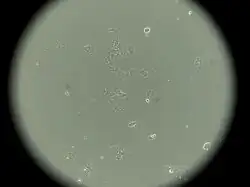

MCF-7

MCF-7 is a breast cancer cell line isolated in 1970 from a 69-year-old woman.[1] MCF-7 is the acronym of Michigan Cancer Foundation-7, referring to the institute in Detroit where the cell line was established in 1973 by Herbert Soule and co-workers.[2] The Michigan Cancer Foundation is now known as the Barbara Ann Karmanos Cancer Institute.[3]

Characteristics of MCF-7 cells

MCF-7 cells have the following characteristics:[2][6][7][9][10][11]

- Primary tumor (invasive breast ductal carcinoma)

- Originate from pleural effusion

- Estrogen receptors present[12]

- Proliferative response to estrogens

- Presence of progesterone receptors

- Contains 17β-estradiol-binding protein[8]

- Cannot have ERBB2 gene amplification (with Her2/neu protein overexpression)

- Tumorigenic in mice but only with estrogen supplementation if engrafted into the subcutaneous fat or mammary fat pad

- Tumorigenic in mice without estrogen supplementation if engrafted intraductally[13]

- Luminal epithelial phenotype

This cell line retained several characteristics of differentiated mammary epithelium, including the ability to process estradiol via cytoplasmic estrogen receptors and the capability of forming domes.